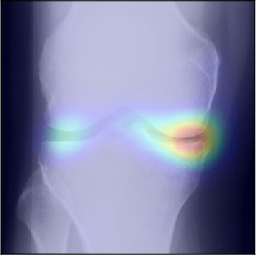

To gain insight into the basis of the CNN’s prediction, we used the GradCAM [24] approach and visualized the attention maps for the well-predicted knees. Examples of attention maps are presented in Figure 5. We observed that in various cases, the CNN paid attention to the compartment opposite to the one where degenerative change became visible during the follow-up visits. Additional examples of such attention maps are presented in Supplementary Figures 3, 4, 5 and 6.

Refer to caption

(a)

(b)

(c)

(d)

Figure 5: Examples of attention maps for progression cases and the corresponding visualization of progression derived using follow-up images from MOST datasets. Here, subplots (a) and (c) show the attention maps derived using a GradCAM approach. Subplots (b) and (d) show the joint-space areas from all the follow-up images (baseline to 84 months). Here, the subplot (b) corresponds to the attention map a) and the subplot (d) corresponds to the attention map (c).